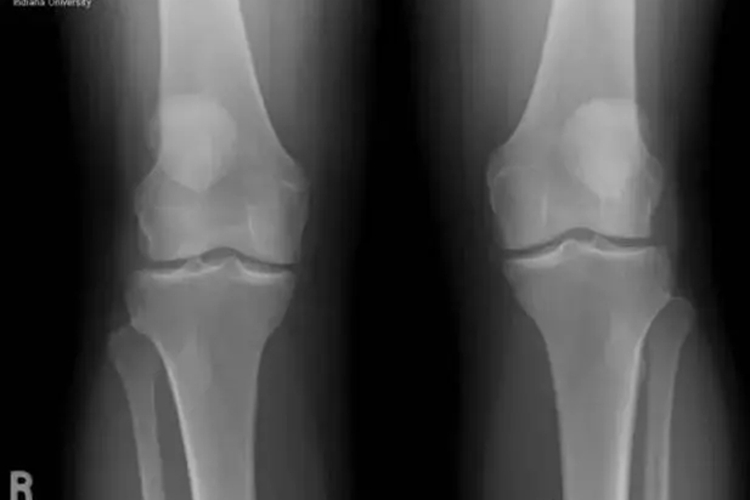

通常表现为腰背酸痛、小腿痉挛、骨质疏松和骨质增生、骨质软化、各类骨折、四肢麻木、记忆力减退、脾气易暴躁、周身乏力等症状。